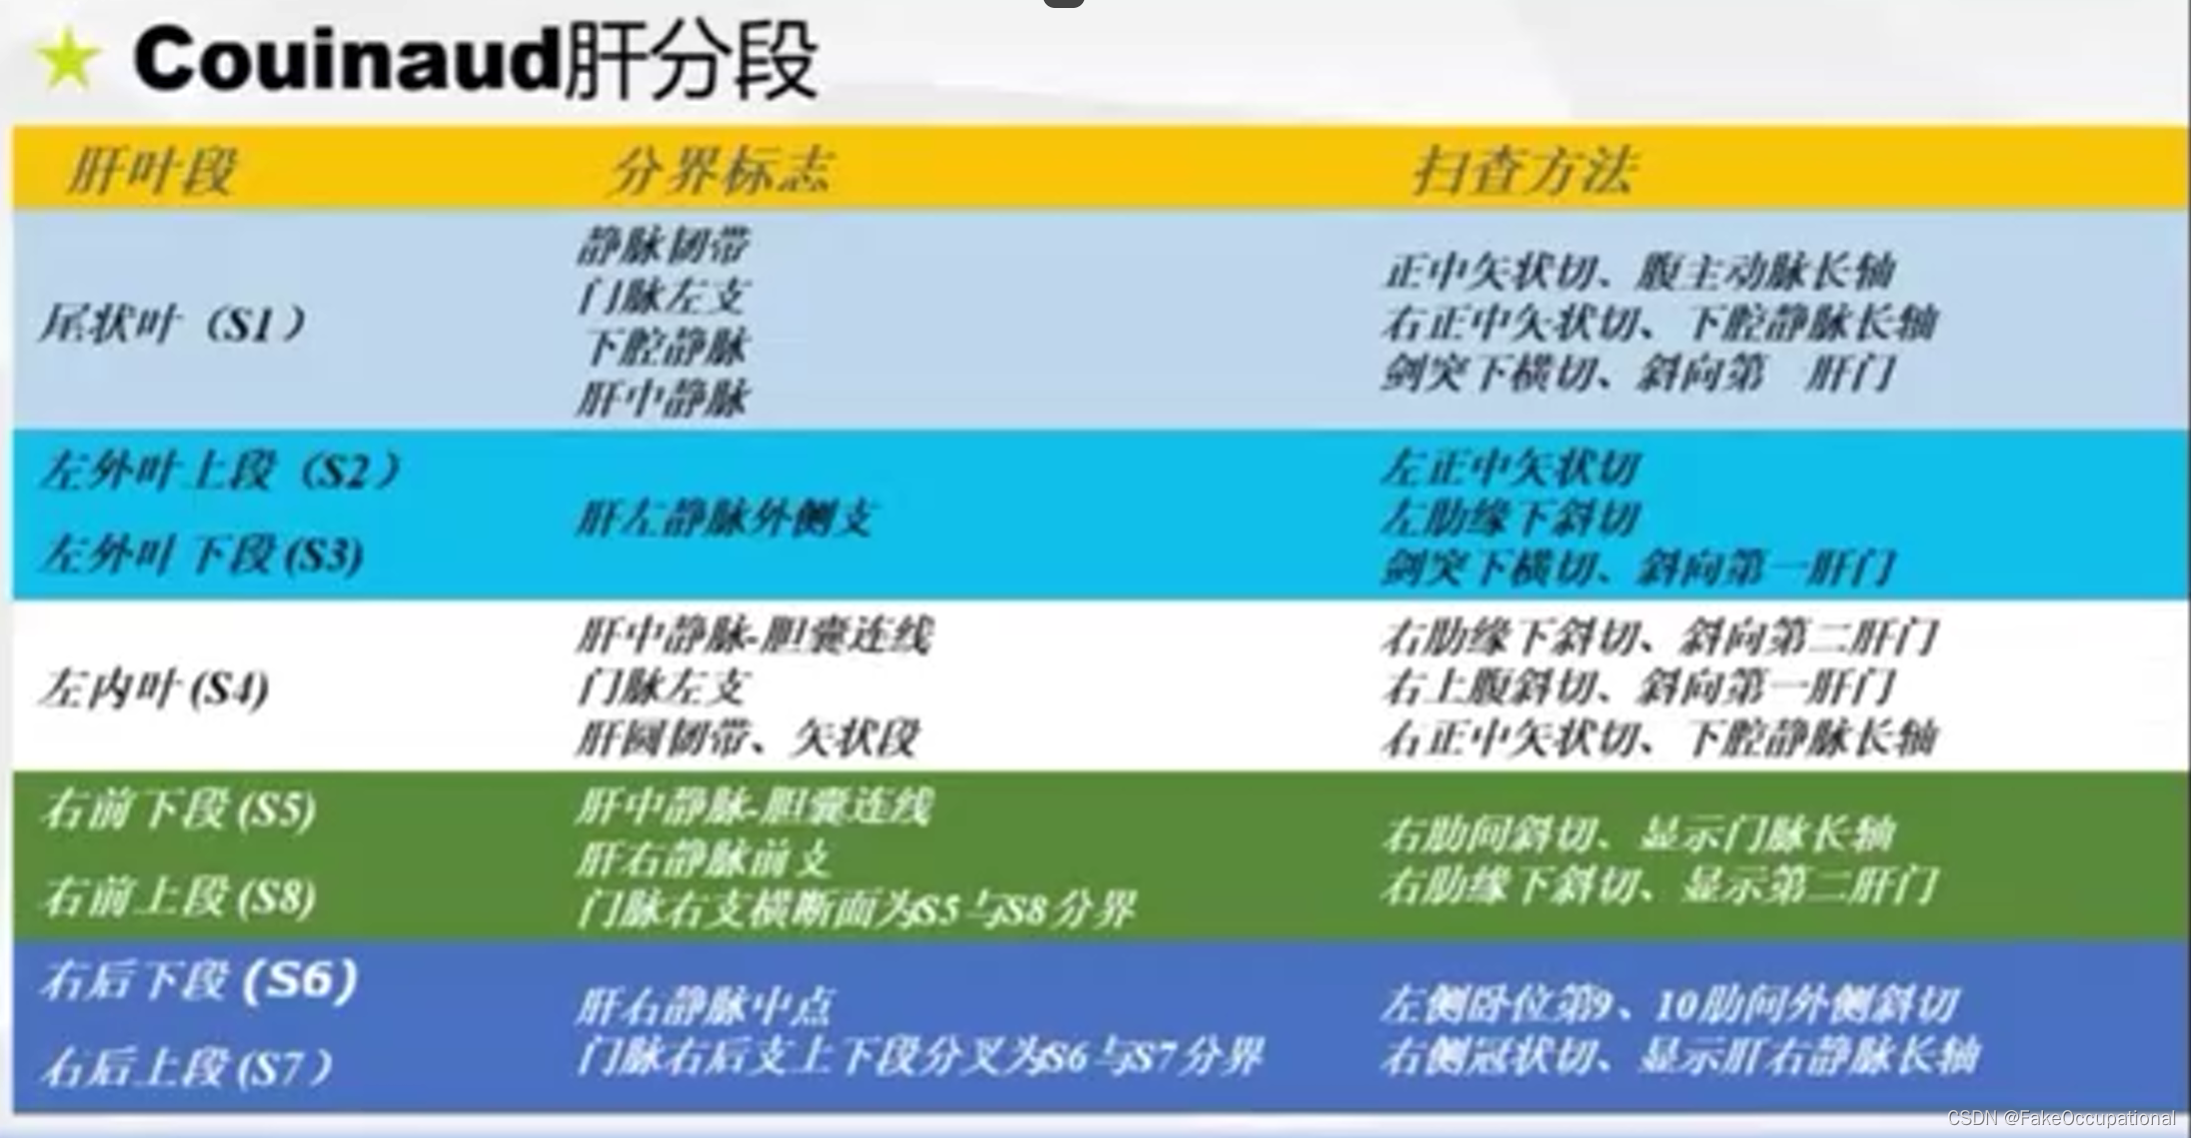

肝脏解剖概要

肝脏超声检查技术